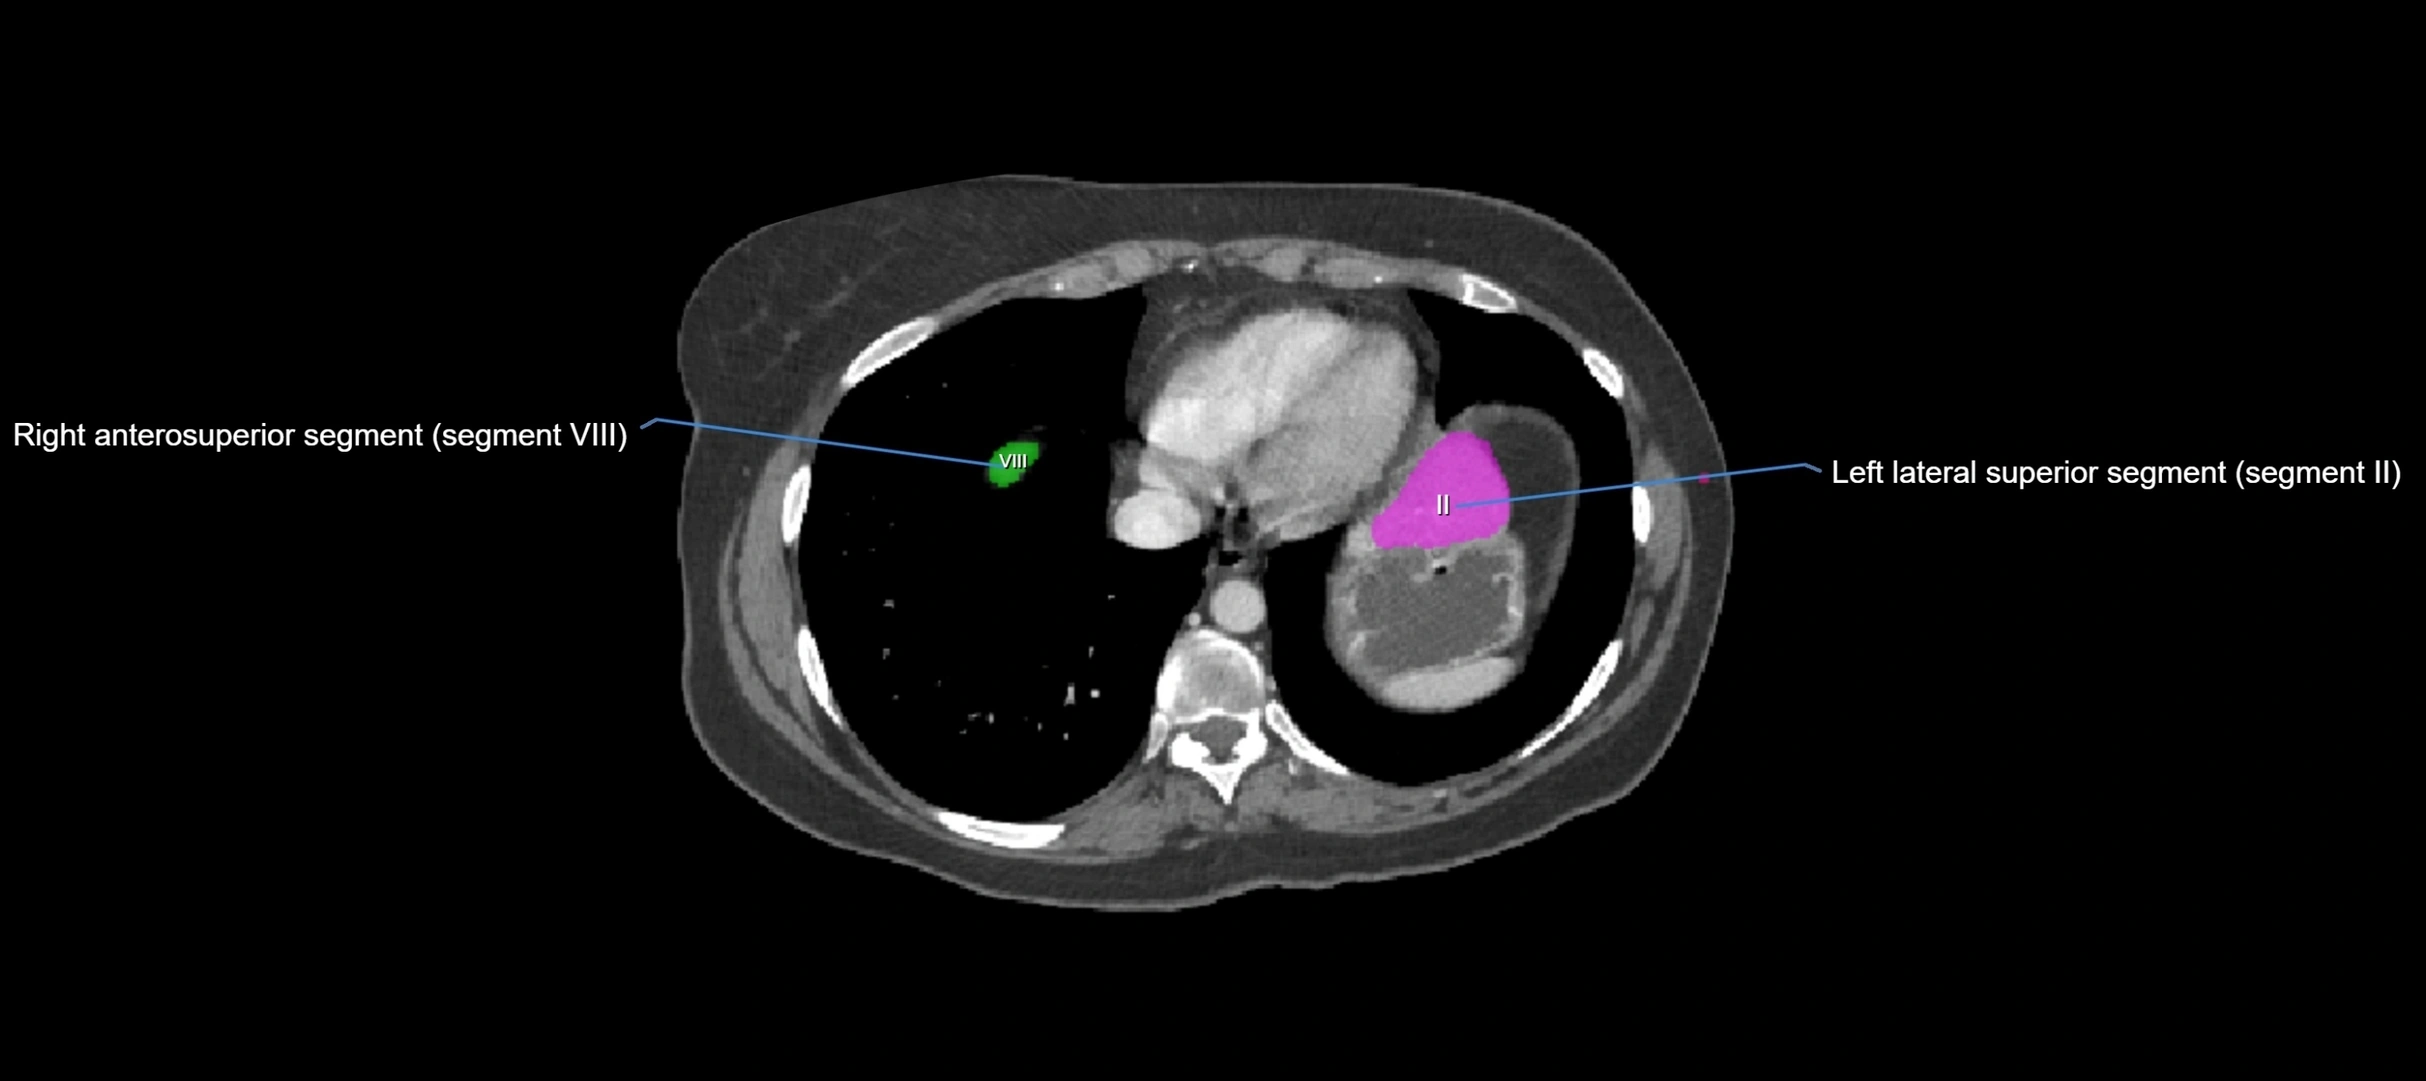

MRI image

image